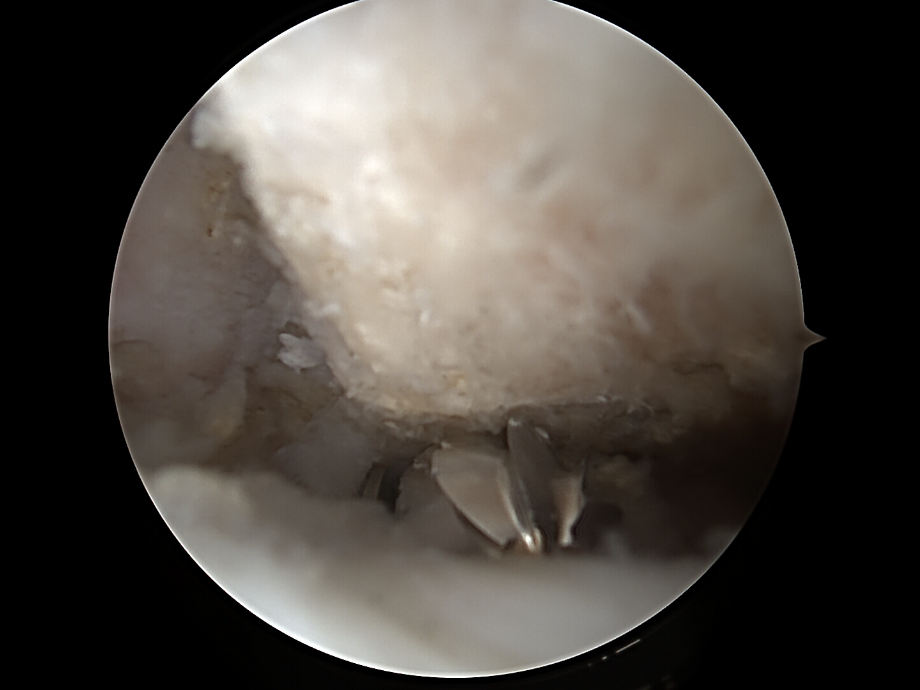

Abtragen der lateralen Clavikula

• Abtragung von ca. 5-10 mm des lateralen Klavikulaendes

• Instrumente:  motorisierte Shaver

• Kontrolle: ausreichender Spalt ohne Knochenkontakt bei Bewegung